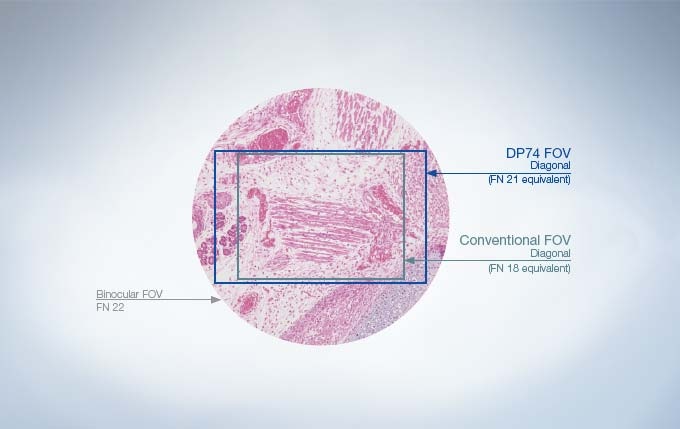

One of the Widest Field of Views Available

The DP74 color fluorescence camera features a field of view that is 37% larger than conventional microscope cameras, which are typically the equivalent of FN 18 or less. The wide 16:10 aspect ratio field of view enables users to find areas of interest more quickly and recognize their position within a sample.